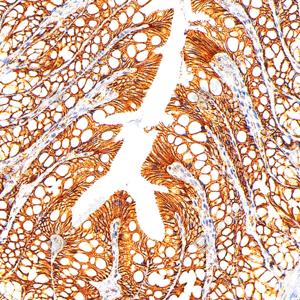

| IHC检测beta Catenin蛋白(货号 GB150016). 样品: 人结肠, 4%多聚甲醛 (货号G1101) 固定12-24小时. 抗原修复: 柠檬酸抗原修复液(干粉, pH 6.0) (G1201), 高压锅均匀喷气计时2分钟. —抗: 1: 500稀释, 4℃ 孵育过夜. 二抗: S-vision免疫组化多聚二抗(山羊抗兔),即用型 (货号G1302), 室温孵育20分钟. |